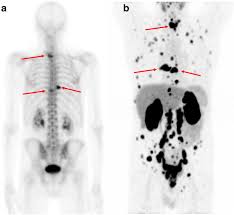

Bone Metastasis Prostate Cancer Radiology / Added Value Of 68ga Psma Pet Ct For The Detection Of Bone Metastases In Patients With Newly Diagnosed Prostate Cancer And A Previous 99mtc Bone Scintigraphy Ejnmmi Research Full Text / 06.03.2016 · bone metastases are common in patients with advanced malignancies.

Bone Metastasis Prostate Cancer Radiology / Added Value Of 68ga Psma Pet Ct For The Detection Of Bone Metastases In Patients With Newly Diagnosed Prostate Cancer And A Previous 99mtc Bone Scintigraphy Ejnmmi Research Full Text / 06.03.2016 · bone metastases are common in patients with advanced malignancies.. Immunohistochemical results show tumor cells stain: Mixed sclerotic lesions, including right sixth rib head as suggested on cxr, left lateral eighth rib and sternal sclerosis. Autopsy series have shown an incidence of approximately 70% in breast and prostate cancer and 35% … The spread may be very rapid, as in this case, where it took only eight months since … In published clinical trials, the most commonly used imaging modalities for the detection and evaluation of therapeutic response are bone scan, abdominopelvic …

Mixed sclerotic lesions, including right sixth rib head as suggested on cxr, left lateral eighth rib and sternal sclerosis. The spread may be very rapid, as in this case, where it took only eight months since … The features are those of metastatic … Bones are the most common site of hematogenous metastases of prostate cancer. 06.03.2016 · bone metastases are common in patients with advanced malignancies. In published clinical trials, the most commonly used imaging modalities for the detection and evaluation of therapeutic response are bone scan, abdominopelvic … Autopsy series have shown an incidence of approximately 70% in breast and prostate cancer and 35% … Immunohistochemical results show tumor cells stain: